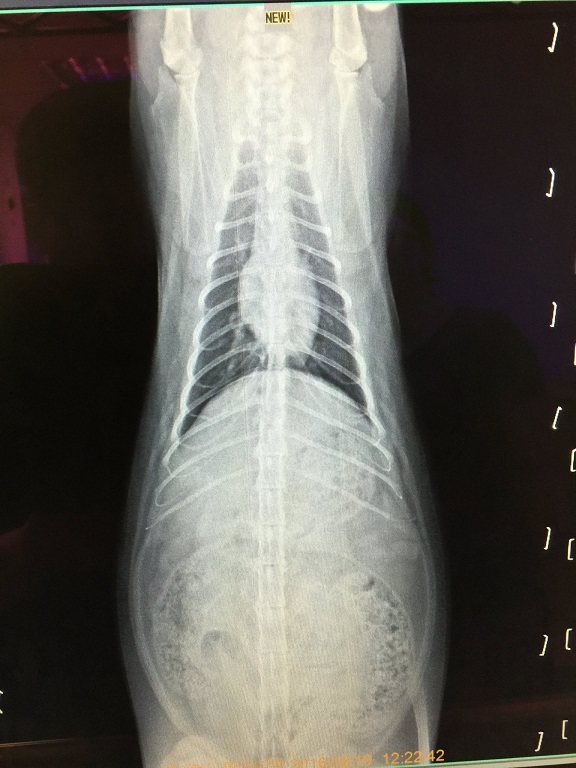

醫生在拔了小君子禿毛處的毛作毛檢後,

發現有黴菌感染的情形,

故開一週份抗黴菌藥。

另外醫生發現小君子最近回診體重越來越輕,

因此幫小君子做了較詳細的血檢、還有胰臟炎檢查,

檢驗結果都正常、沒有胰臟炎,

醫生拍X光照片後並沒發現異常,

而後懷疑是否可能是感染心絲蟲導致嚴重咳嗽的情況,